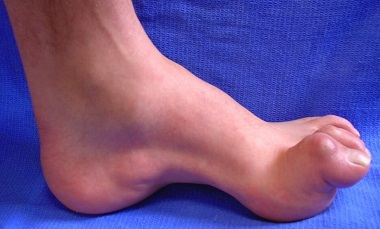

Şarko-Mari-Tuts xəstəliyi Könül İsmayilova, Nabil Seyidov, Lətafət Dadaşova